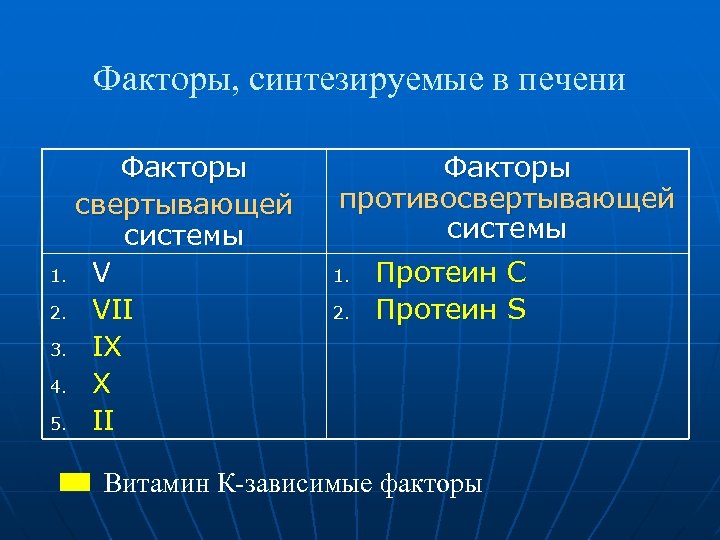

Факторы, синтезируемые в печени Факторы свертывающей системы 1. V 2. VII 3. IX 4. X 5. II Факторы противосвертывающей системы 1. 2. Протеин С Протеин S Витамин К-зависимые факторы